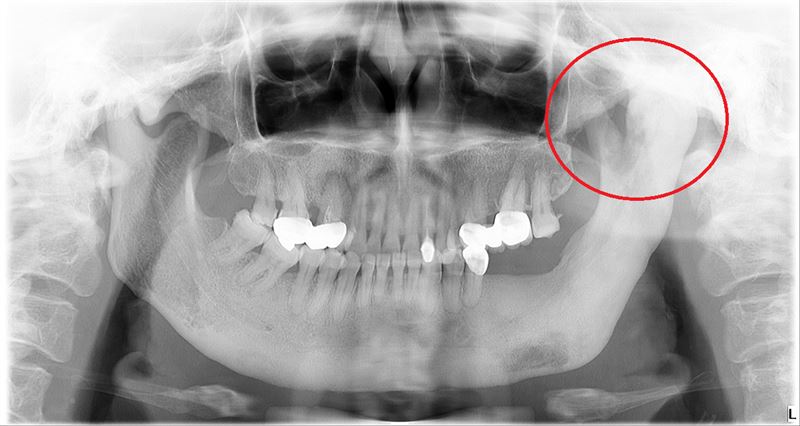

許博智指出,纖維增生不良發生時,骨頭會不規則地肆意增生,導致骨骼變形,若壓迫到神經則會疼痛,例如他所收治的1名50多歲張姓女子,將近20年前因左臉頰腫脹疼痛到其他醫院就醫,當時診斷為骨髓炎,並服藥緩解症狀。

後來張姓女子狀況加劇,輾轉來到台北慈濟醫院,許博智替她進行病理切片,診斷為纖維增生不良,由於病人不想手術,所以利用定期注射藥劑的方式,暫時抑制增生情況。

許博智表示,近期這名患者的病情惡化,纖維增生部位蔓延,導致左側顳顎關節融合鈣化,嘴巴幾乎無法張開,吃飯平均要花2個小時,甚至連吃茶葉蛋都沒辦法,且經常痛到難以入睡,嚴重影響生活品質。

經與患者討論後,許博智決定透過3D導航定位系統進行骨骼修形手術,並在術中取出顎骨,進行液態氮冷凍治療、根除病灶,術後已能開口進食,生活品質提升。